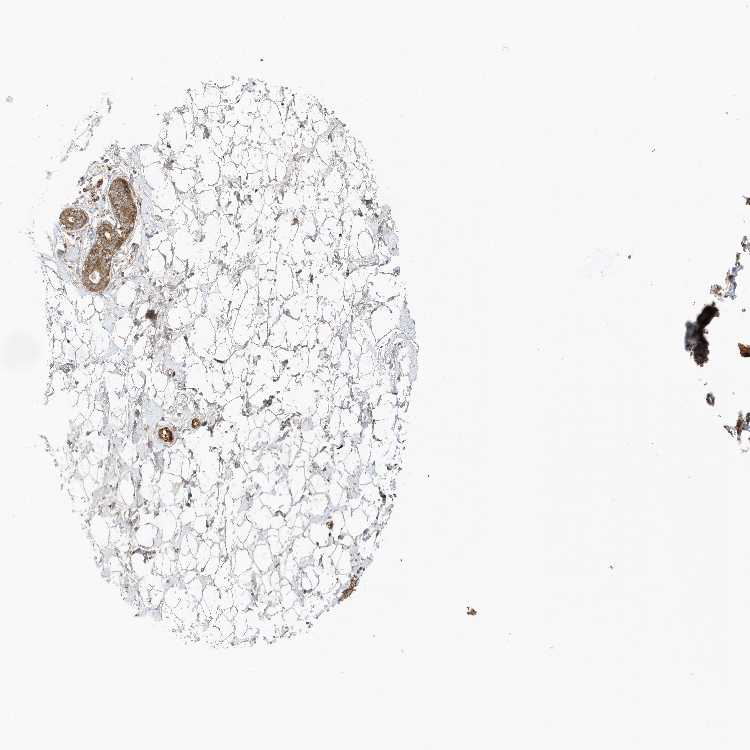

BREAST - Antibody stainingi

Antibody staining in the annotated cell types in the current human tissue is reported as not detected, low, medium, or high, based on conventional immunohistochemistry profiling in selected tissues. This score is based on the combination of the staining intensity and fraction of stained cells.

Each image is clickable and will lead to virtual microscopy that enables deeper exploration of all samples and also displays staining intensity scores, fraction scores and subcellular localization as well as patient and tissue information for each sample.

Antibody HPA035514Antibody HPA035515

Adipocytes MediumMedium

Glandular cells MediumMedium

Myoepithelial cells MediumMedium